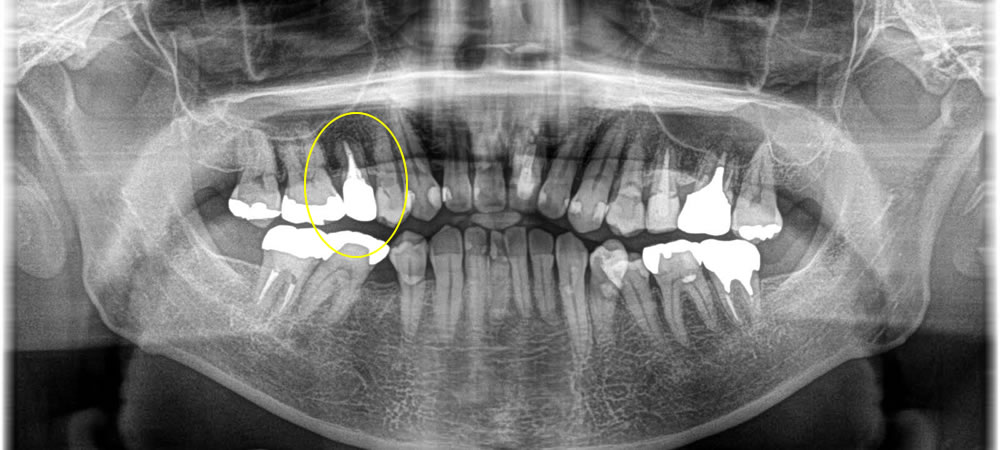

歯と歯の間の虫歯を除去しセラミックインレーで修復した症例

年齢

30代

性別

男性